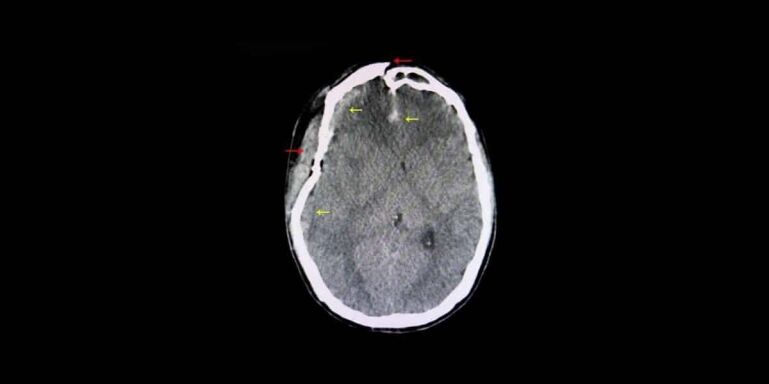

The brain can experience movement inside the skull so suddenly that it hits both inside walls. In other words, both sides of the brain are injured. This is incredibly dangerous. It’s a major cause of brain swelling after a car accident and can even lead to bleeding in the brain itself. There may be skull fractures associated with it. A crash in which the car rolls over is a likely cause of this injury.